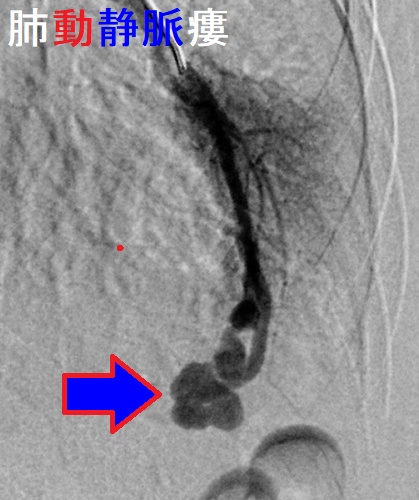

甲状腺癌肺転移により肺動静脈瘻(pulmonary arteriovenous fistula)ができると、

- 肺胞での酸素・二酸化炭素交換をすることなく、肺動脈から肺静脈へのシャントができるため、呼吸困難・チアノーゼ・多血症・バチ指、右心不全、脳虚血

- 肺というフィルターを介さずに、静脈から動脈に血栓・菌が通り抜けて脳に行き、脳梗塞・脳膿瘍

あるいは、菌が心臓に行き、感染性心内膜炎

- 肺動静脈瘻の血管壁は脆く、破裂して喀血・血胸

(MedTimes1979;107:87―92.)

[Am J Surg. 1964 Sep;108:416-8.][N Engl J Med. 1959 Apr 30;260(18):901-7.]

欧米において肺動静脈瘻の10-70%は遺伝性で、遺伝性出血性毛細血管拡張(オスラー・ウェーバー・ランデュ病)に合併しますが、日本では10-20%程度です。(日本臨床 別冊呼吸器症候群Ⅱ:374-378,2009)

大きな無症候性肺動静脈奇形と結節性甲状腺腫・甲状腺乳頭癌が合併して、甲状腺乳頭癌肺転移との鑑別を要した報告があります。[Indian J Nucl Med. 2020 Oct 21;35(4):326–329.]

肺動静脈瘻自体は、無症状時、胸部エックス線写真や胸部単純CT画像から偶然、発見されることが多い。しかし、喀血、脳梗塞・脳膿瘍の危険性が高いため、3 mm 以上は治療適応。経カテーテル塞栓術。